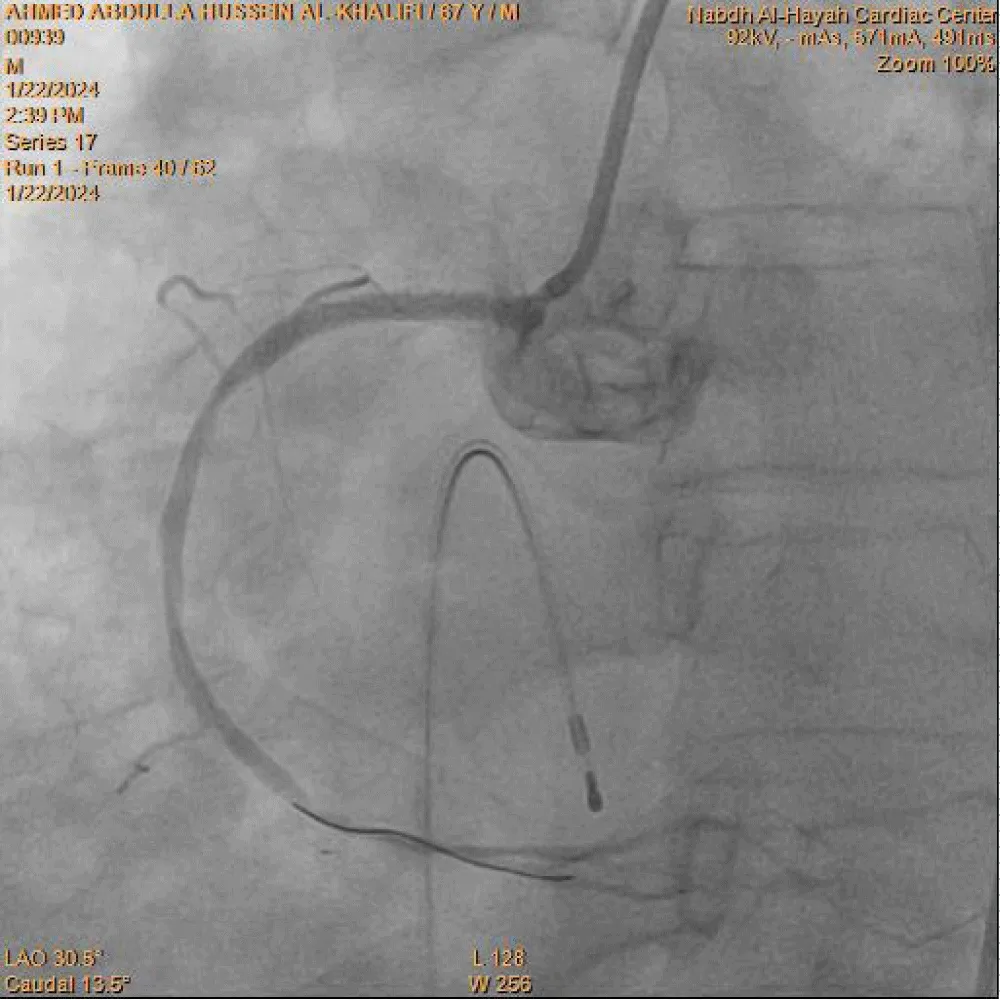

Coronary angiography was carried out using a 6-Fr diagnostic left Judkins catheter, which revealed an atherosclerotic left coronary system. A right Judkins guiding catheter was then used to cannulate the right coronary artery (RCA), demonstrating total occlusion of the proximal RCA with a high thrombus burden. The occluded segment was successfully crossed with a 0.014-inch BMW PTCA floppy guidewire. Limited thrombus aspiration was achieved after five passes using a 6-Fr Export aspiration catheter (Medtronic), as shown in Figure 3. Control angiography of the RCA after thrombus aspiration demonstrated TIMI I flow. Subsequently, a 1.25 × 10 mm Sprinter balloon (Medtronic Inc.) was advanced over the guidewire for balloon predilatation. Upon reaching the proximal RCA, three radiopaque markers were visualized instead of the expected two (Figure 4). This immediately raised suspicion of a device fracture. Careful inspection of the Export catheter, which had just been withdrawn from the guiding catheter and was lying on the table, confirmed loss of its distal tip. This represented a precarious situation, with a thrombogenic broken catheter fragment retained within a thrombus-laden coronary artery and loss of operator control over the fragment.

Given the very short distance between the distal balloon marker and the third radiopaque marker, it was inferred that only the distal tip of the Export catheter had fractured (Figure 5). An attempt to advance a smaller 1.0 × 10 mm Sprinter balloon distal to the retained fragment over the original guidewire was unsuccessful. Therefore, a second BMW PTCA guidewire was advanced into the distal RCA. A 2.0 × 12 mm Sprinter PTCA balloon was then advanced and positioned distal to the fractured catheter tip. The balloon was inflated to 8 atm and gently withdrawn from the mid to proximal RCA, successfully entrapping and retrieving the broken Export catheter tip into the guiding catheter.

The entire system, including the guiding catheter, both BMW PTCA guidewires, the balloon, and the fractured aspiration catheter tip, was removed en bloc. The guiding catheter was flushed with heparinized saline, and the retrieved broken catheter tip was clearly identified. The RCA was subsequently re-engaged using a new JR 3.5 guiding catheter, and a fresh BMW PTCA guidewire successfully crossed the proximal RCA lesion. Predilatation was performed using a 2.0 × 12 mm Sprinter balloon, restoring TIMI III flow. A 3.0 × 30 mm drug-eluting stent was then deployed in the proximal RCA and inflated to 14 atm. Final angiography demonstrated TIMI III flow with good stent expansion and no evidence of edge dissection (Figure 6).